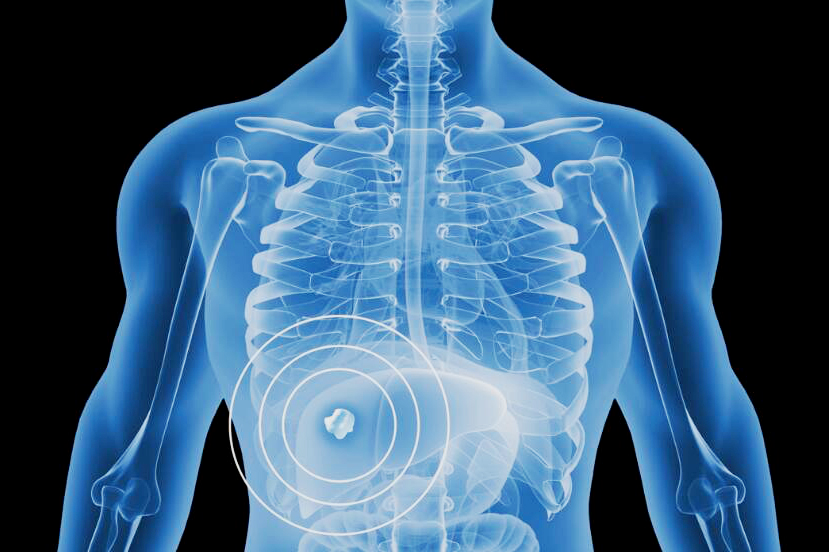

钇90树脂微球它的治疗原理,就是通过一次微创介入手术,把数百万个钇90微球注射至滋养肝脏肿瘤的动脉血管,微球随血液进入肿瘤内部,让钇90释放的β射线近距离杀死肿瘤细胞。

由于β射线平均穿透距离仅为2.5毫米,减少了对正常肝脏组织和毗邻器官损伤,而且肝动脉的血流量高,大部分放射性物质均由肝肿瘤吸收,正常细胞接收极少,这种治疗方式更直接、更精准,而且最大程度避免了传统化疗放疗方式“杀敌一千,自损八百”带来的损伤。

钇90树脂微球被注入患者肝脏血管后,会释放高能量β放射线,可近距离对肿瘤细胞实施精准打击,且对肝脏周围的正常组织没有影响。